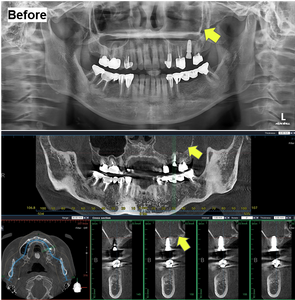

At the two-month follow-up, a panoramic radiograph and cone beam CT (CBCT) were obtained for comprehensive evaluation. Radiographic analysis showed that the prior radiopacity in the left maxillary sinus had resolved into radiolucency, suggesting resolution of the inflammation and restoration of sinus health.

Before & After